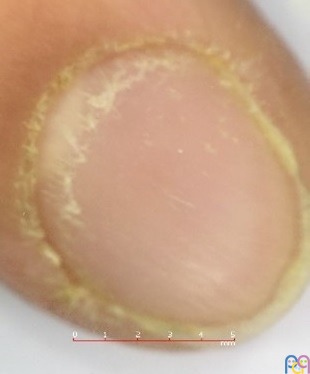

Se presenta el caso de un paciente de 10 años, sin antecedentes de interés, salvo prematuridad de 35 semanas. Acude a consulta para valoración de uñas deslustradas con aparente pitting en ambas manos (Figura 1 y Figura 2) de varios meses de evolución. Presenta una exploración física sin hallazgos y sin lesiones ungueales en los pies. Se reevalúa al paciente en varias ocasiones sin presentar mejoría, por lo que ante la evolución tórpida se decide iniciar estudio.

Se hace también interconsulta con Dermatología, que recomienda tratamiento tópico con corticoide y emoliente cada 24 horas durante 10 días en las lesiones ungueales. Tras finalizar el tratamiento, el paciente presenta persistencia de las lesiones. Ante la evolución tórpida se realiza de nuevo interconsulta a Dermatología, que informa de probable traquioniquia de las 20 uñas, recomendando tratamiento tópico con corticoide (metilprednisolona aceponato) en uña y zona periungueal. Tras dos meses de tratamiento, se reevalúa al paciente, impresionando de mejoría de la rugosidad y del pitting, especialmente a la palpación del lecho ungueal (Figura 3).

Existen dos subtipos diferentes de traquioniquia. El primero se conoce como traquioniquia opaca, es el subtipo más grave y caracterizado por uñas ásperas. El segundo subtipo es la traquioniquia brillante, en la que encontramos uñas brillantes u opalescentes con numerosas fositas (pitting). Este es el subtipo que presenta nuestro paciente. El subtipo de traquioniquia brillante se encuentra más frecuentemente relacionado con alopecia areata2,4.

El diagnóstico es clínico, teniendo en cuenta el diagnóstico diferencial con otras patologías ungueales, como la onicomicosis2. El primer paso es realizar una anamnesis completa, incluyendo antecedentes personales y familiares de trastornos de la piel, seguido de una exploración física de toda la superficie cutánea y mucosas. Puede resultar de ayuda el uso de la onicoscopia por mejor visualización de los patrones dermatoscópicos6. No suele realizarse biopsia ungueal, al tratarse de un proceso benigno. Las alteraciones que se han descrito en la biopsia consisten en leve infiltrado inflamatorio superficial con espongiosis de la matriz ungueal2,5,6.